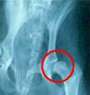

骨盤の凹みが浅く、大腿骨の先が抜けそうな股関節形成不全。![]() 正常例。 ![]() |

食生活の改善などで病気の進行をくいとめることが不可能だと、残された手段は外科手術である。同じ股関節形成不全でも、それほど症状が悪くなければ、骨盤部の骨を3カ所(恥骨と挫骨と腸骨)切って、股関節の凹みの側の角度を変え、大腿骨の先(骨頭)が脱臼しにくいように整形する手術(3点骨切り術という)がある。しかし症状が悪化して変形性関節症となり、自然脱臼をおこしてしまうほどになれば、人工関節を使った股関節全置換手術をほどこさざるを得ない。それは、骨盤部の凹み部分に樹脂製のカップを付け、大腿骨の先を切断して。ステンレス製の骨頭を埋め込む大手術である。 これまで、その人工関節の輸入がむずかしく、手術自体も難手術のために、日本国内で股関節全置換手術を行うケースはごくわずかだった。最近は国内で人工関節が入手できるようになったが、その値段がきわめて高く、また手術経験の豊富な獣医師が少ないために、まだまだ一般化するまでに時間がかかるのが現実だ。そのほか、もっと簡便な手術方法として、大腿骨の先(骨頭)を切断して取りのぞいてしまう方法がある。骨が自然治癒する形で繊維性のじょうぶな結合組織による「偽関節」ができるのを待つわけである。 いずれにしても、外科手術は最後の手段である。できるなら、愛犬がわずかに「びっこ」をひく状態で発見し、かかりつけの獣医師に相談して、食事管理を手始めに症状の悪化を防ぐ対策をとっていくべきだ。先のアメリカ人獣医師によれば、たとえ股関節形成不全であろうとも、犬自身が痛みを感じずに動き回っているなら、あえて手術をする必要はないという。飼い主は必要以上に悲観的にならず、同時に問題点に目をつぶらず、現実を冷静に見つめて、どうすることがほんとうに愛犬のためになるか、を獣医師と一緒に手探りしていくしか道はない。 |